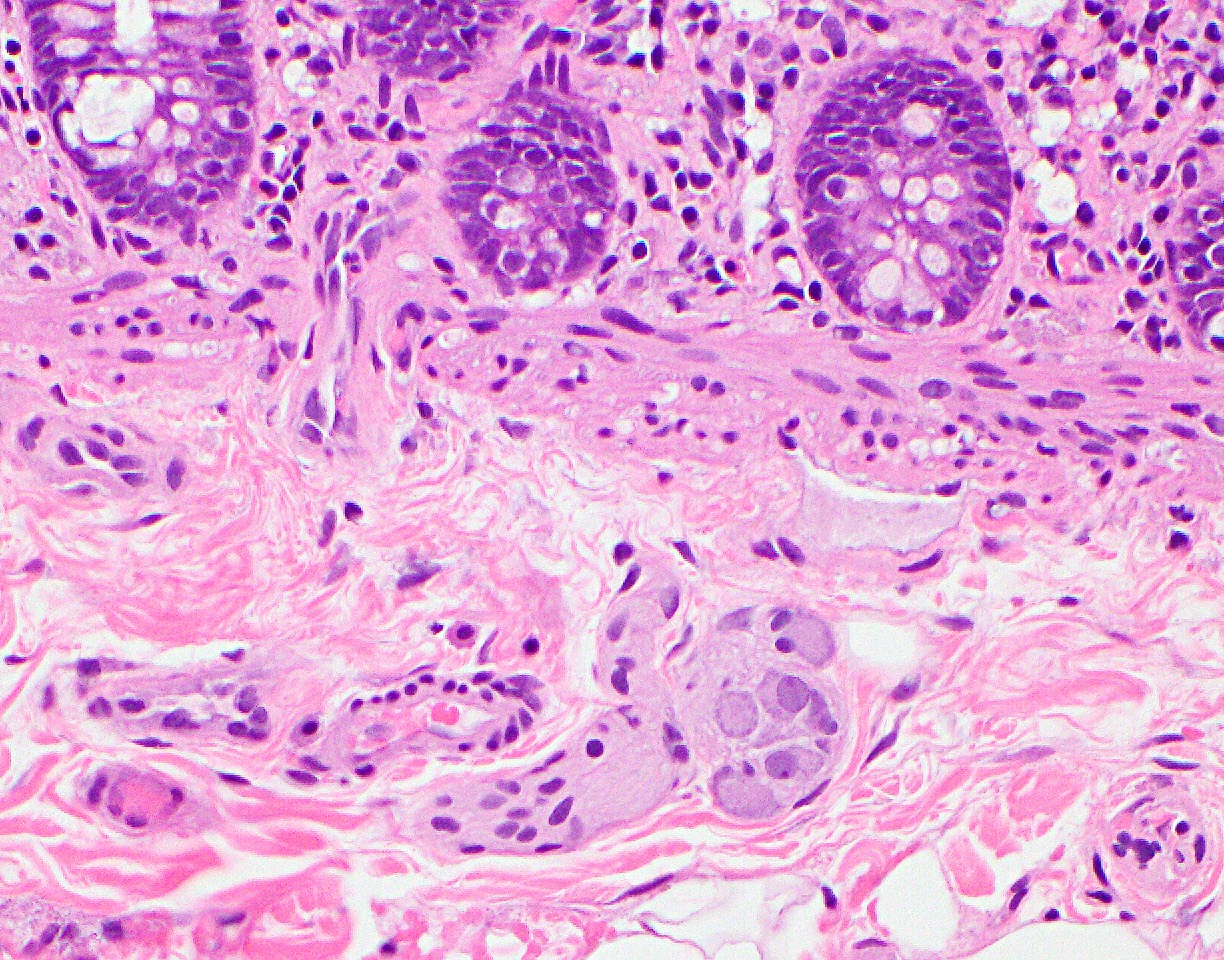

Microscopic (histologic) description

- Mucosa is composed of the epithelium, lamina propria and muscularis mucosa

- Epithelium: colonic epithelium is composed of a single layer of the absorptive columnar cells and the goblet cells

- As the epithelium invaginates into the underlying lamina propria, it forms glandular structures called crypts, arranged in a characteristic parallel test tube-like pattern

- Crypt is a functional unit of colon and is primarily lined by the goblet cells

- Crypt also has enteroendocrine cells, Paneth cells and stem cells located at its base

- During the maturation process, the mature epithelial cells migrate toward the surface of the epithelium (luminal migration), while the immature (stem cells) are at the base of the crypts

- On maturation, the Paneth cells migrate to the base of the crypt, instead of the luminal migration

- Enteroendocrine cells also stay in the deeper portion of the crypt and in the middle of the tubule

- Absorptive cells: predominant cells in the right colon

- Columnar cells with eosinophilic cytoplasm, basally located nuclei, small apical mucin vacuoles and apical microvilli

- Primarily line the surface epithelium

- Goblet cells: predominant cells in the left colon

- Large cells with intracytoplasmic mucin and basally located hyperchromatic nuclei

- Mucin composition of goblet cells is different from the mucin in the absorptive cells (Histopathology 2000;37:561)

- Other cell types of the epithelium:

- Enteroendocrine cells:

- Located at the base of the crypts and have eosinophilic secretory granules in the cytoplasm with apically located nuclei

- Apical location of the nuclei helps to differentiate these cells from the Paneth cells

- Paneth cells:

- Paneth cells have a triangular shape with densely eosinophilic cytoplasmic granules

- Nuclei are basally located, unlike enteroendocrine cells described above, a distinction important in the left colon, since the presence of Paneth cells in this part of colon is abnormal and could be a sign of chronic injury

Microscopic (histologic) images

D. Paneth cells. They have a triangular shape with densely eosinophilic cytoplasmic granules and basally located nuclei, as opposed to enteroendocrine cells (see image above). Their presence in the left side of the colon can be a sign of inflammatory bowel disease.